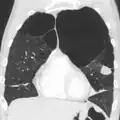

A CT scan is not routinely used except for the exclusion of bronchiectasis.[5] Pulse oximetry measurement of peripheral oxygen saturation is recommended in people with clinical signs of respiratory failure or right heart failure.[5] An analysis of arterial blood is recommended in those with a peripheral oxygen saturation of 92% or less to determine actual blood oxygen level and assess for high levels of carbon dioxide in the blood, which may have therapeutic implications such as need for non-invasive ventilation or oxygen supplementation.[10] WHO recommends that all those diagnosed with COPD be screened for alpha-1 antitrypsin deficiency.[40]

A severe case of bullous emphysema -

Very severe emphysema with lung cancer on the left (CT scan)